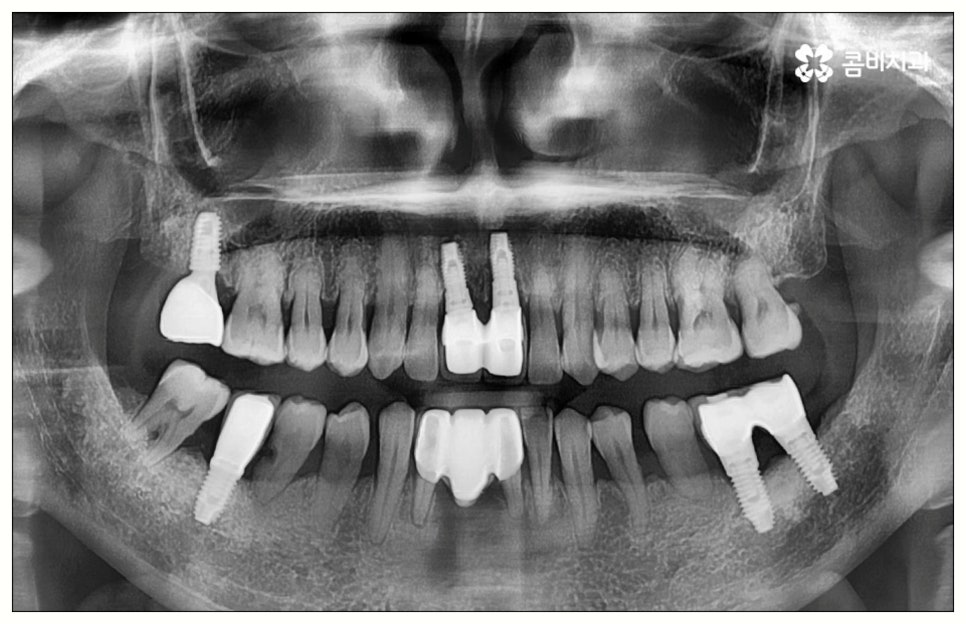

그러나 모든 환자분들이 원데이임플란트 방식을 이용할 수 있는 것은 아니기 때문에 주의하실 필요가 있어요. 말씀드렸던 것처럼 임플란트 수술은 직접 환자의 잇몸뼈에 식립을 진행하는 방식의 치료이기 때문에 잇몸뼈 상태가 양호하지 않은 분들의 경우 발치 후 바로 임플란트를 심는 것이 식립 성공률이나 지속적인 안정성 측면에서 좋지 않을 수 있어요. 특히 잇몸 질환으로 인해 염증이 심한 경우 또는 바탕이 되는 잇몸뼈의 밀도나 높이가 많이 부족한 경우에는 원데이임플란트 방식이 불가능하다고 할 수 있는데요.

이때 만약 무리하게 즉시 식립을 진행하게 되면 임플란트 치아가 제대로 기능하기 어려울 뿐 아니라 주위염 등 부작용을 일으킬 가능성이 높아 주변 잇몸 및 치아에도 좋지 않은 영향을 주게 되며 결국 임플란트가 흔들리거나 빠지면서 재수술이 필요한 상황까지 이를 수 있으므로 필요한 치료부터 선행하는 것이 좋을 거예요. 위에서 예로 든 상황이라면 잇몸 염증을 먼저 꼼꼼하게 치료한 후 또는 뼈이식술을 통해 안정성을 높인 후에 임플란트 식립을 진행하실 필요가 있어요. 이 과정에서 무엇보다 중요한 것은 수술 전 3D CT를 통해 환자의 상태를 정확하고 꼼꼼하게 확인하고, 환자의 연령, 치아를 상실하게 된 원인 및 시기, 식습관 등 관련된 모든 부분을 빠짐없이 검토하여 각자에게 꼭 맞는 계획을 세운 다음 회복 정도를 체크해 가면서 무리하지 않게 진행해 나가는 것이기 때문에 정밀 진단 장비 및 숙련된 의료진이 있는 치과에서 임플란트 치료를 받으시도록 권유드리고 있습니다.